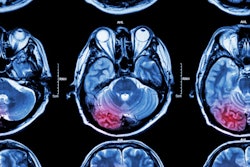

First image: Low-dose CT with filtered back projection (FBP) at 0.8 mGy appears grainy and noisy. Second image: Same CT postprocessed was rated diagnostic quality by independent radiologists. All images courtesy of Algomedica.